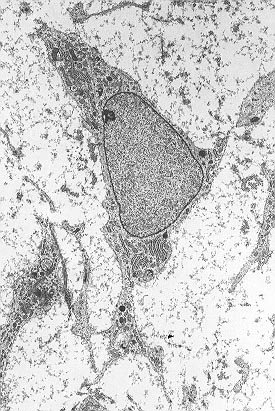

![]() خلية جذعية باللحمة المتوسطة تبين typical ultrastructural morphology. | |

الخلايا الجذعية المتعلقة باللُحمة المتوسطة إنگليزية: Mesenchymal Stem Cells هي خلايا جذعية بالغة لها القابلية على التمايز إلى عدة أنواع من الخلايا وأهمها: الخلايا بانية العظام والخلايا العضلية والخلايا الغضروفية والخلايا الشحمية والخلايا العصبية. يمكن الحصول على هذه الخلية من نخاع العظم.